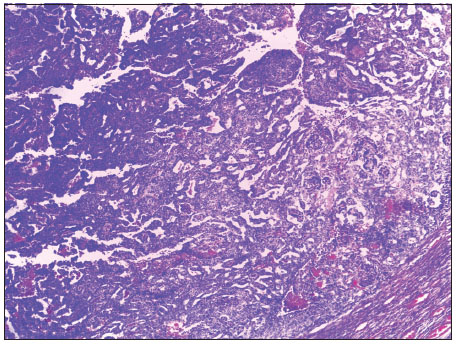

Eight months after completion of treatment, he developed right-sided neck swelling with a cough, progressive weight loss, and night sweats over 6 weeks. He had a chest CT scan which confirmed a mediastinal mass, and lymph node biopsy confirmed (lymphocyte rich) classical Hodgkin's lymphoma. He had a bone marrow aspirate and trephine biopsy which were clear of the disease. He subsequently received two courses of vincristine, etoposide, prednisolone, and doxorubicin (OEPA) and four courses of cyclophosphamide, vincristine, prednisolone, dacarbazine (COPDAC) and is currently on follow-up since completing treatment. Pictorial representation is shown in [Figure 4], [Figure 5], [Figure 6].

| Figure 4 Hodgkin’s lymphoma. Low-power photomicrograph showing parenchymal architectural disarray. (H and E, ×40)